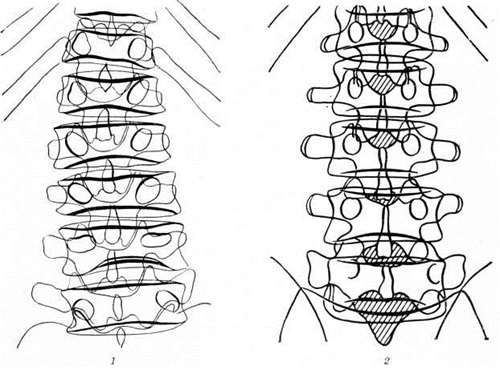

Моркио болезньМоркио болезнь (L. Morquio, уругвайский педиатр, 1867—1935; синонимы: Мукополисахаридоз тип IV, синдром Моркио — Брейлсфорда, множественный энхондральный дизостоз, деформирующая остеохондродистрофия) — наследственное заболевание соединительной ткани из группы мукополисахаридозов, характеризующееся множественными поражениями скелета, низким ростом, кератансульфатурией. Заболевание впервые описали в 1929 год независимо друг от друга Моркио и Брейлсфорд (J. F. Brailsford). До 1959 год к Моркио болезнь относили различные множественные поражения скелета, в том числе спондилоэпифизарную дисплазию, множественную эпифизарную дисплазию и другие В самостоятельную нозологический форму Моркио болезнь выделена после обнаружения специфического биохимический признака — наличия в моче мукополисахаридов. Частота Моркио болезнь примерно 1 : 40 000 среди новорожденных. Этиология и патогенез. Тип наследования — аутосомно-рецессивный. Патогенез связан с нарушением катаболизма кислых гликозамингликанов (мукополисахаридов) вследствие дефицита фермента — хондроитинсульфата-N-ацетил-гексозоаминсульфатсульфатазы. Клиническая картина. Первые симптомы появляются к концу первого — началу второго года жизни. Наблюдается гротескность черт лица, гипертелоризм (смотри полный свод знаний Дизостоз), седловидный нос, мегалоглоссия, мышечная слабость, отставание в двигательном развитии. Отмечается диффузная гипотрофия и дряблость мышц, изменение походки от лёгкой хромоты до утиной. К 3—4 годам формируются грубые костно-суставные деформации грудной клетки (куриная, бочкообразная, килеобразная), позвоночника (сколиоз и кифосколиоз), вальгусная деформация конечностей (рисунок 1). Замедляется темп роста, шея и туловище — короткие. К 7 —10 годам у некоторых детей появляются боли в конечностях, возникают контрактуры в локтевых, плечевых, коленных суставах. Миопатический симптомокомплекс нарастает; дети жалуются на слабость, утомляемость в состоянии покоя, снижение мышечной силы. Определяются признаки внутричерепной гипертензии (смотри полный свод знаний Гипертензивный синдром), вегетативная лабильность, повышение сухожильных рефлексов вследствие постепенного развития центральных парезов и параличей (смотри полный свод знаний Параличи, парезы). Психическое развитие, как правило, нормальное. При осмотре глазного дна выявляется атрофия диска зрительного нерва (смотри полный свод знаний). Диагноз устанавливается на основании клинические, картины, биохимический исследования мочи и рентгенологическое данных. В моче обнаруживается избыточная экскреция общего количества кислых гликозамингликанов, в частности кератансульфата. При рентгенологическое исследовании длинных и коротких трубчатых костей наблюдается нарушение роста эпифизов костей, проявляющееся в их уплощении, расширении и уменьшении высоты (рисунок 2) при отсутствии существенного торможения роста в эпифизарных хрящах. При рентгенографии позвоночника, как правило, обнаруживается заметное уплощение и расширение тел позвонков от CII до Lv — платибрахиспондилия (рисунок 3), чем и объясняется характерное укорочение туловища и необычно короткая шея при Моркио болезнь; межпозвоночные диски при этом мало изменены или не изменены вовсе. Переднезадний размер грудной клетки увеличен, межрёберные промежутки сужены, грудина дугообразно деформирована. Все эти изменения выявляются при обзорной (желательно телевизионной) рентгеноскопии с последующей обязательной рентгенографией тех отделов скелета, в которых обнаруживаются наиболее выраженные изменения. Дифференциальный диагноз следует проводить с другими типами мукополисахаридозов (смотри полный свод знаний), несовершенным остеогенезом (смотри полный свод знаний Остеогенез несовершенный), спондилоэпифизарными и метафизарными дисплазиями, витамин D-резистентным рахитом (смотри полный свод знаний Фосфат-диабет), почечным рахитом (смотри полный свод знаний Остеопатия нефрогенная), врождённым сифилисом (смотри полный свод знаний), гипотиреозом (смотри полный свод знаний). Лечение. Лечению подлежат больные с легкоустранимыми или стойкими деформациями конечностей, контрактурами, анкилозом суставов в порочном положении, вывихами и подвывихами в суставах, приводящими к нарушениям формы и функции конечностей. Лечение может быть консервативное и оперативное. Выбор метода лечения зависит от тяжести заболевания, возраста и общего состояния больного. |

Рис. 1. | ||